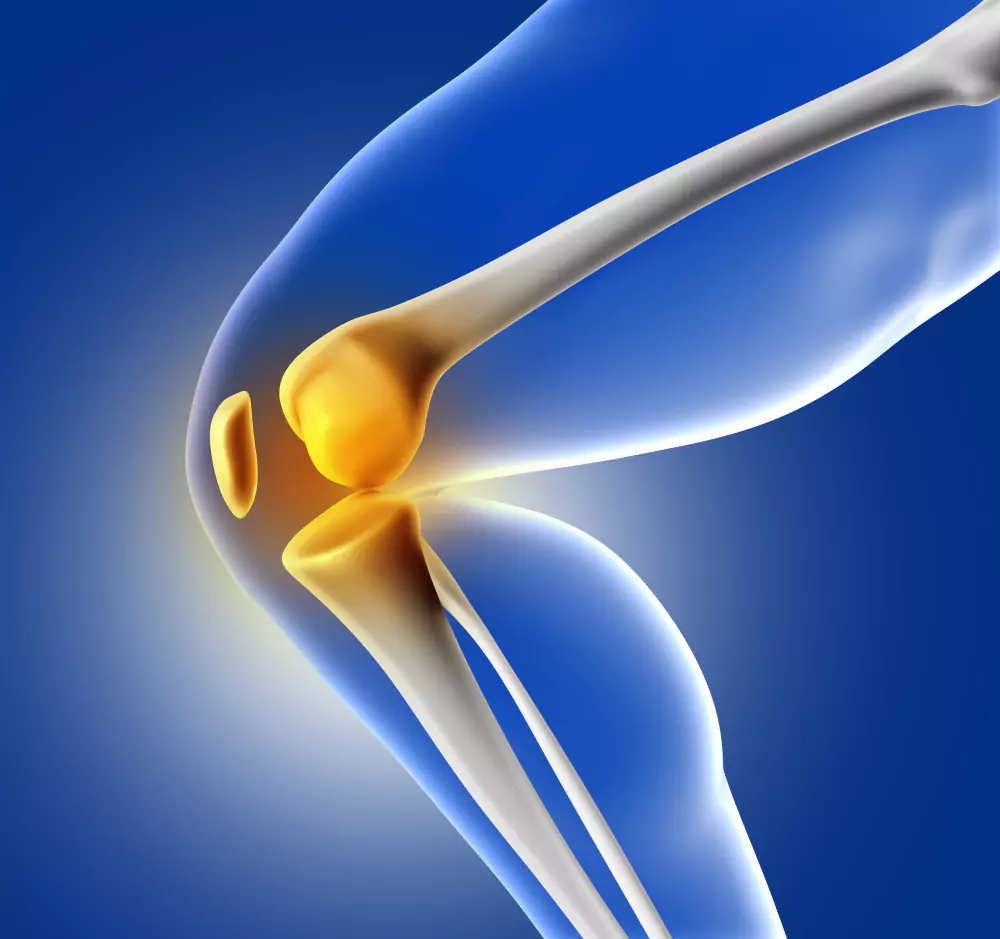

Tibial Osteotomy (Knee Realignment) is a specialized orthopedic procedure designed to correct knee alignment issues, relieve joint pain, and delay or prevent the progression of osteoarthritis. It involves surgically cutting and reshaping the tibia (shinbone) to redistribute weight across the knee joint, reducing stress on damaged cartilage. Under the expertise of Dr. Nithin Kumar Bejjanki, patients benefit from precise surgical planning, minimally invasive techniques, and personalized rehabilitation programs, enabling pain relief, improved mobility, and enhanced joint function.

The goal is to realign the knee, relieve stress on damaged cartilage, and preserve joint longevity.

Tibial osteotomy reduces pressure on affected knee compartments, improves function, and delays the need for total knee replacement.